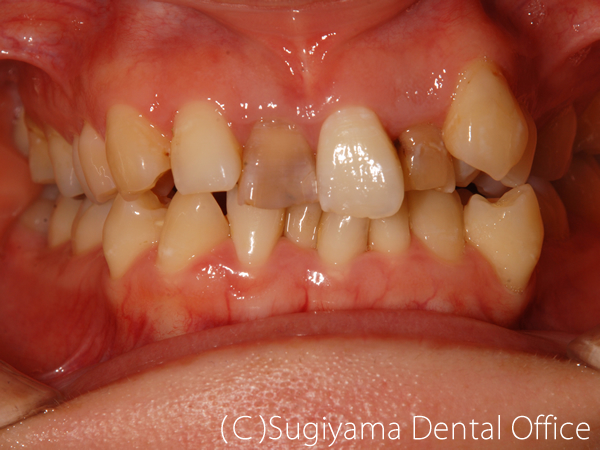

前歯を綺麗にしてほしいということで来院した女性の患者さんです。

親知らずは抜歯しましたが、そのほかは1本も歯を抜かずに矯正治療を仕上げました。

変色が著しかった前歯2本はオールセラミッククラウンで治しました。

歯が綺麗になったことで、笑顔がさらに美しくなりました。